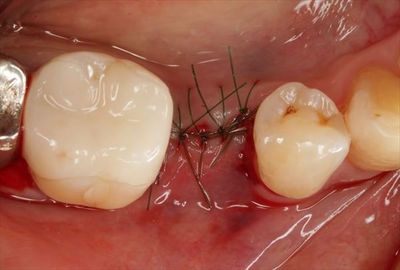

骨吸収を防ぐため、デコルチケーション後にハイドロキシアパタイトを填入します。

![]()

減張切開後に縫合封鎖しました。